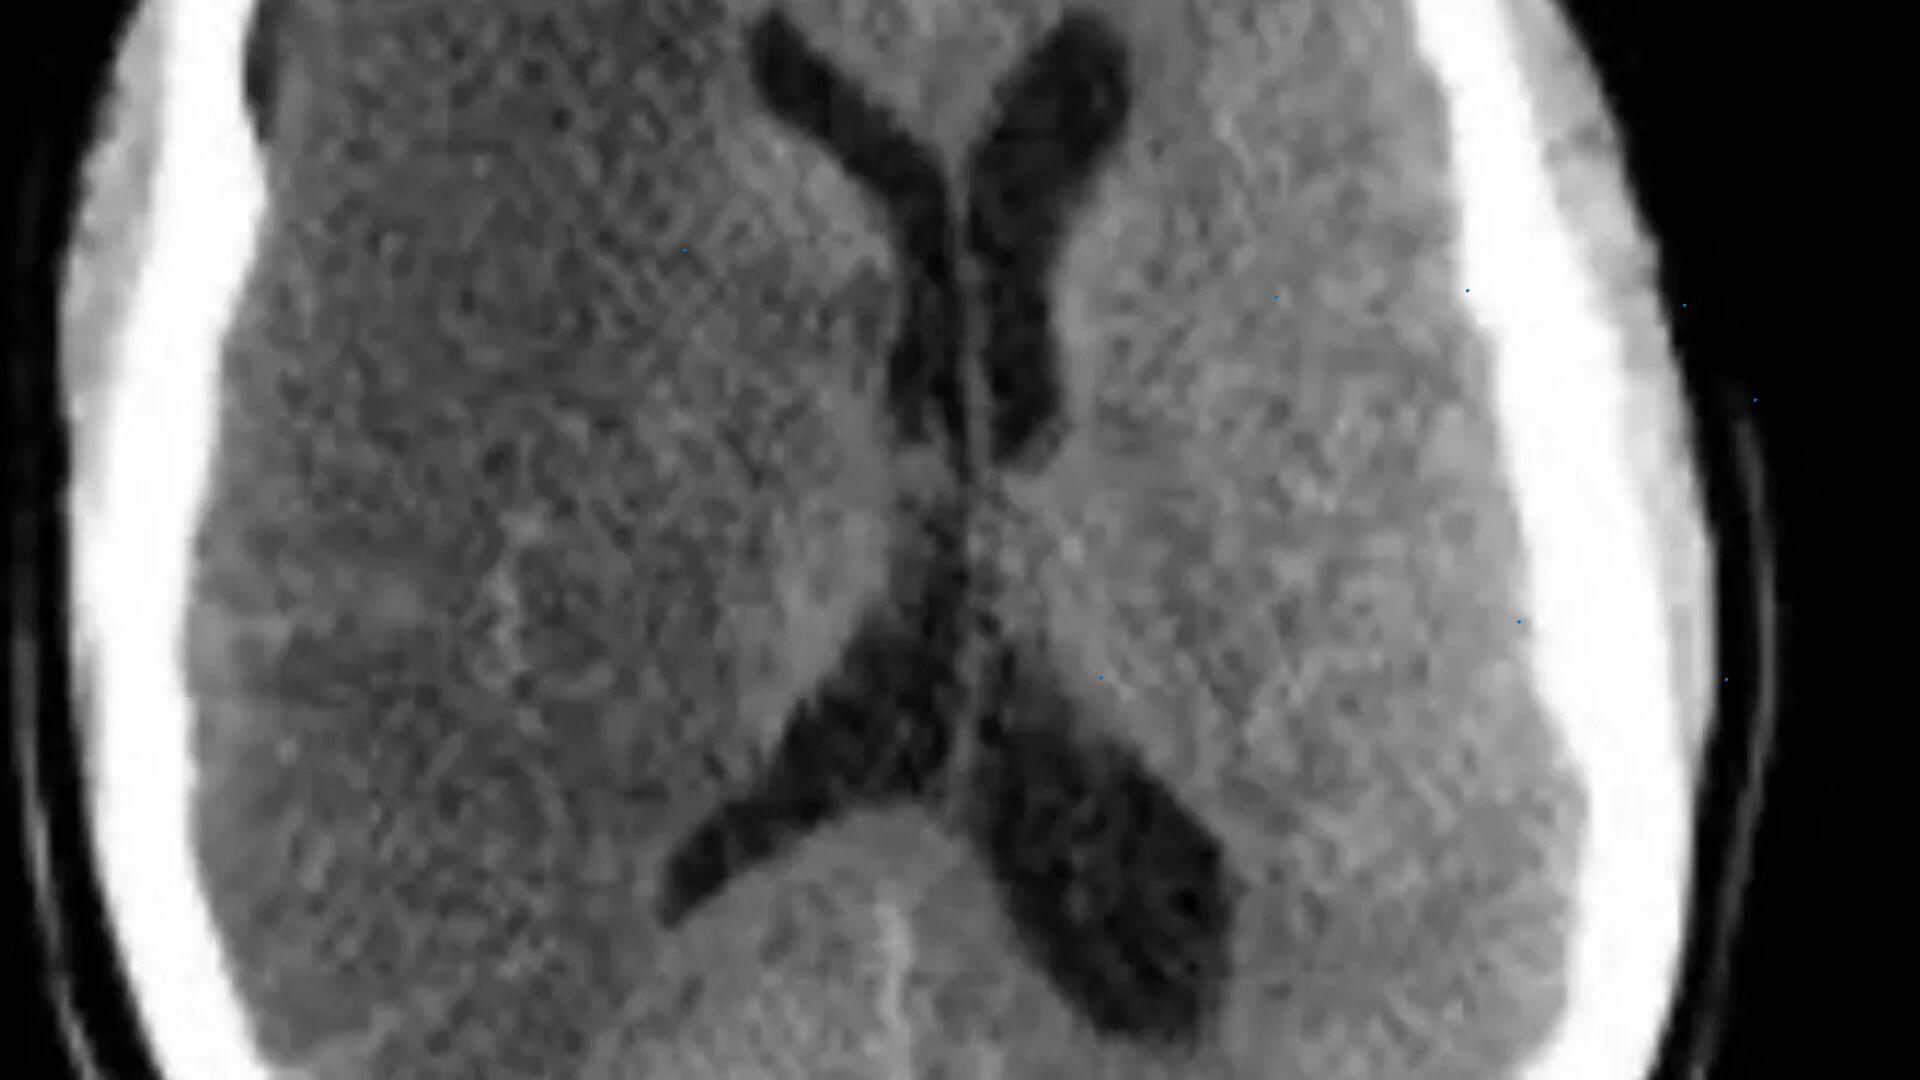

Jovem, adepta de exercícios físicos e sem histórico de comorbidade. Essa é a descrição da professora de educação física, de 34 anos, que sofreu um AVC (Acidente Vascular Cerebral), na última segunda-feira (7), durante aula de exercícios aeróbicos, em uma academia de Campo Grande.

O caso chama a atenção porque a profissional de educação física contrapõe o perfil de vitimas de ACV, doença que – conforme dados do Portal da Transparência do CRC (Centro de Registro Civil) – de janeiro ao início de abril deste ano matou 217 pessoas em Mato Grosso do Sul.

Além dos fatores de riscos, também existem casos de AVC relacionados à genética. Porém, um quadro – ainda não explicado – intriga os especialistas: o caso de AVC em pessoas jovens e saudáveis, como aconteceu com a professora de educação física.

Segundo a neurologista, AVC relacionado ao fator de risco tem 90% de chance de ser evitado com tratamento adequado das comorbidades. No entanto, situações semelhantes ao caso da professora de educação física, não podem ser prevenidos.

“Não é comum, mas pode acontecer e, infelizmente, esses são os casos que não conseguimos prevenir”, frisa.